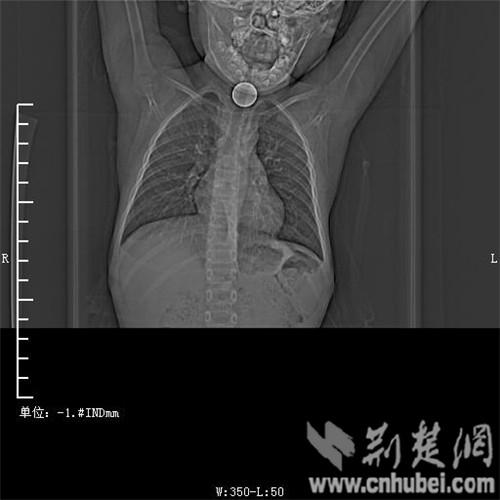

圖為:硬幣卡在了陽(yáng)陽(yáng)的喉部

2015年1月4日下午,湖北英山一6歲男童在學(xué)校玩耍時(shí),無(wú)意將硬幣卡入吼中,嘔吐不止幾近窒息,緊急轉(zhuǎn)診至武漢市普仁醫(yī)院后,硬幣已被取出。專家提醒,家長(zhǎng)應(yīng)注意教育孩子不能吞含異物,避免悲劇發(fā)生。

消化內(nèi)主任方向明告訴記者,孩子送來(lái)時(shí)已經(jīng)是晚上8點(diǎn)15分,醫(yī)護(hù)人員立即給孩子拍胸部CT確定硬幣的位置,8點(diǎn)30分,方向明通過(guò)胃鏡下食管異物取出術(shù),成功的將這枚一元硬幣取了出來(lái)。1月5日上午,陽(yáng)陽(yáng)順利出院,醫(yī)生護(hù)士在他出院時(shí)不斷告訴他,以后千萬(wàn)不要吞含異物。